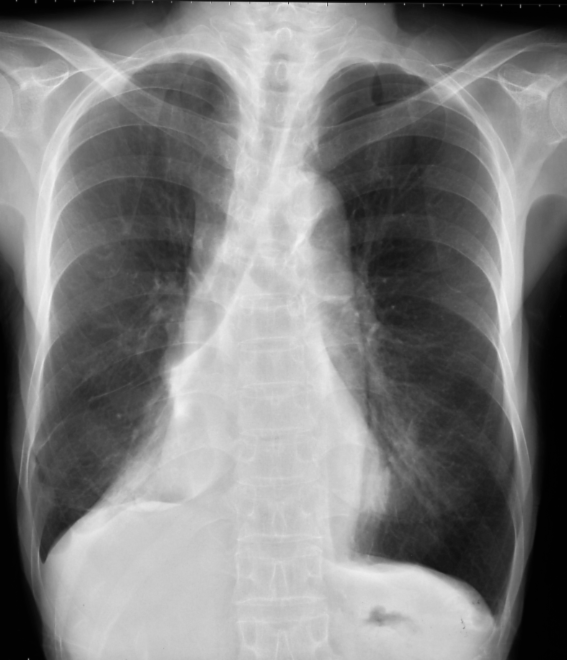

右上葉の無気肺の胸部単純X線写真

胸部正面写真で傍気管線が消失し、縦隔上部のシルエットが消失し(シルエットサイン陽性)、気管が右側に偏位している。